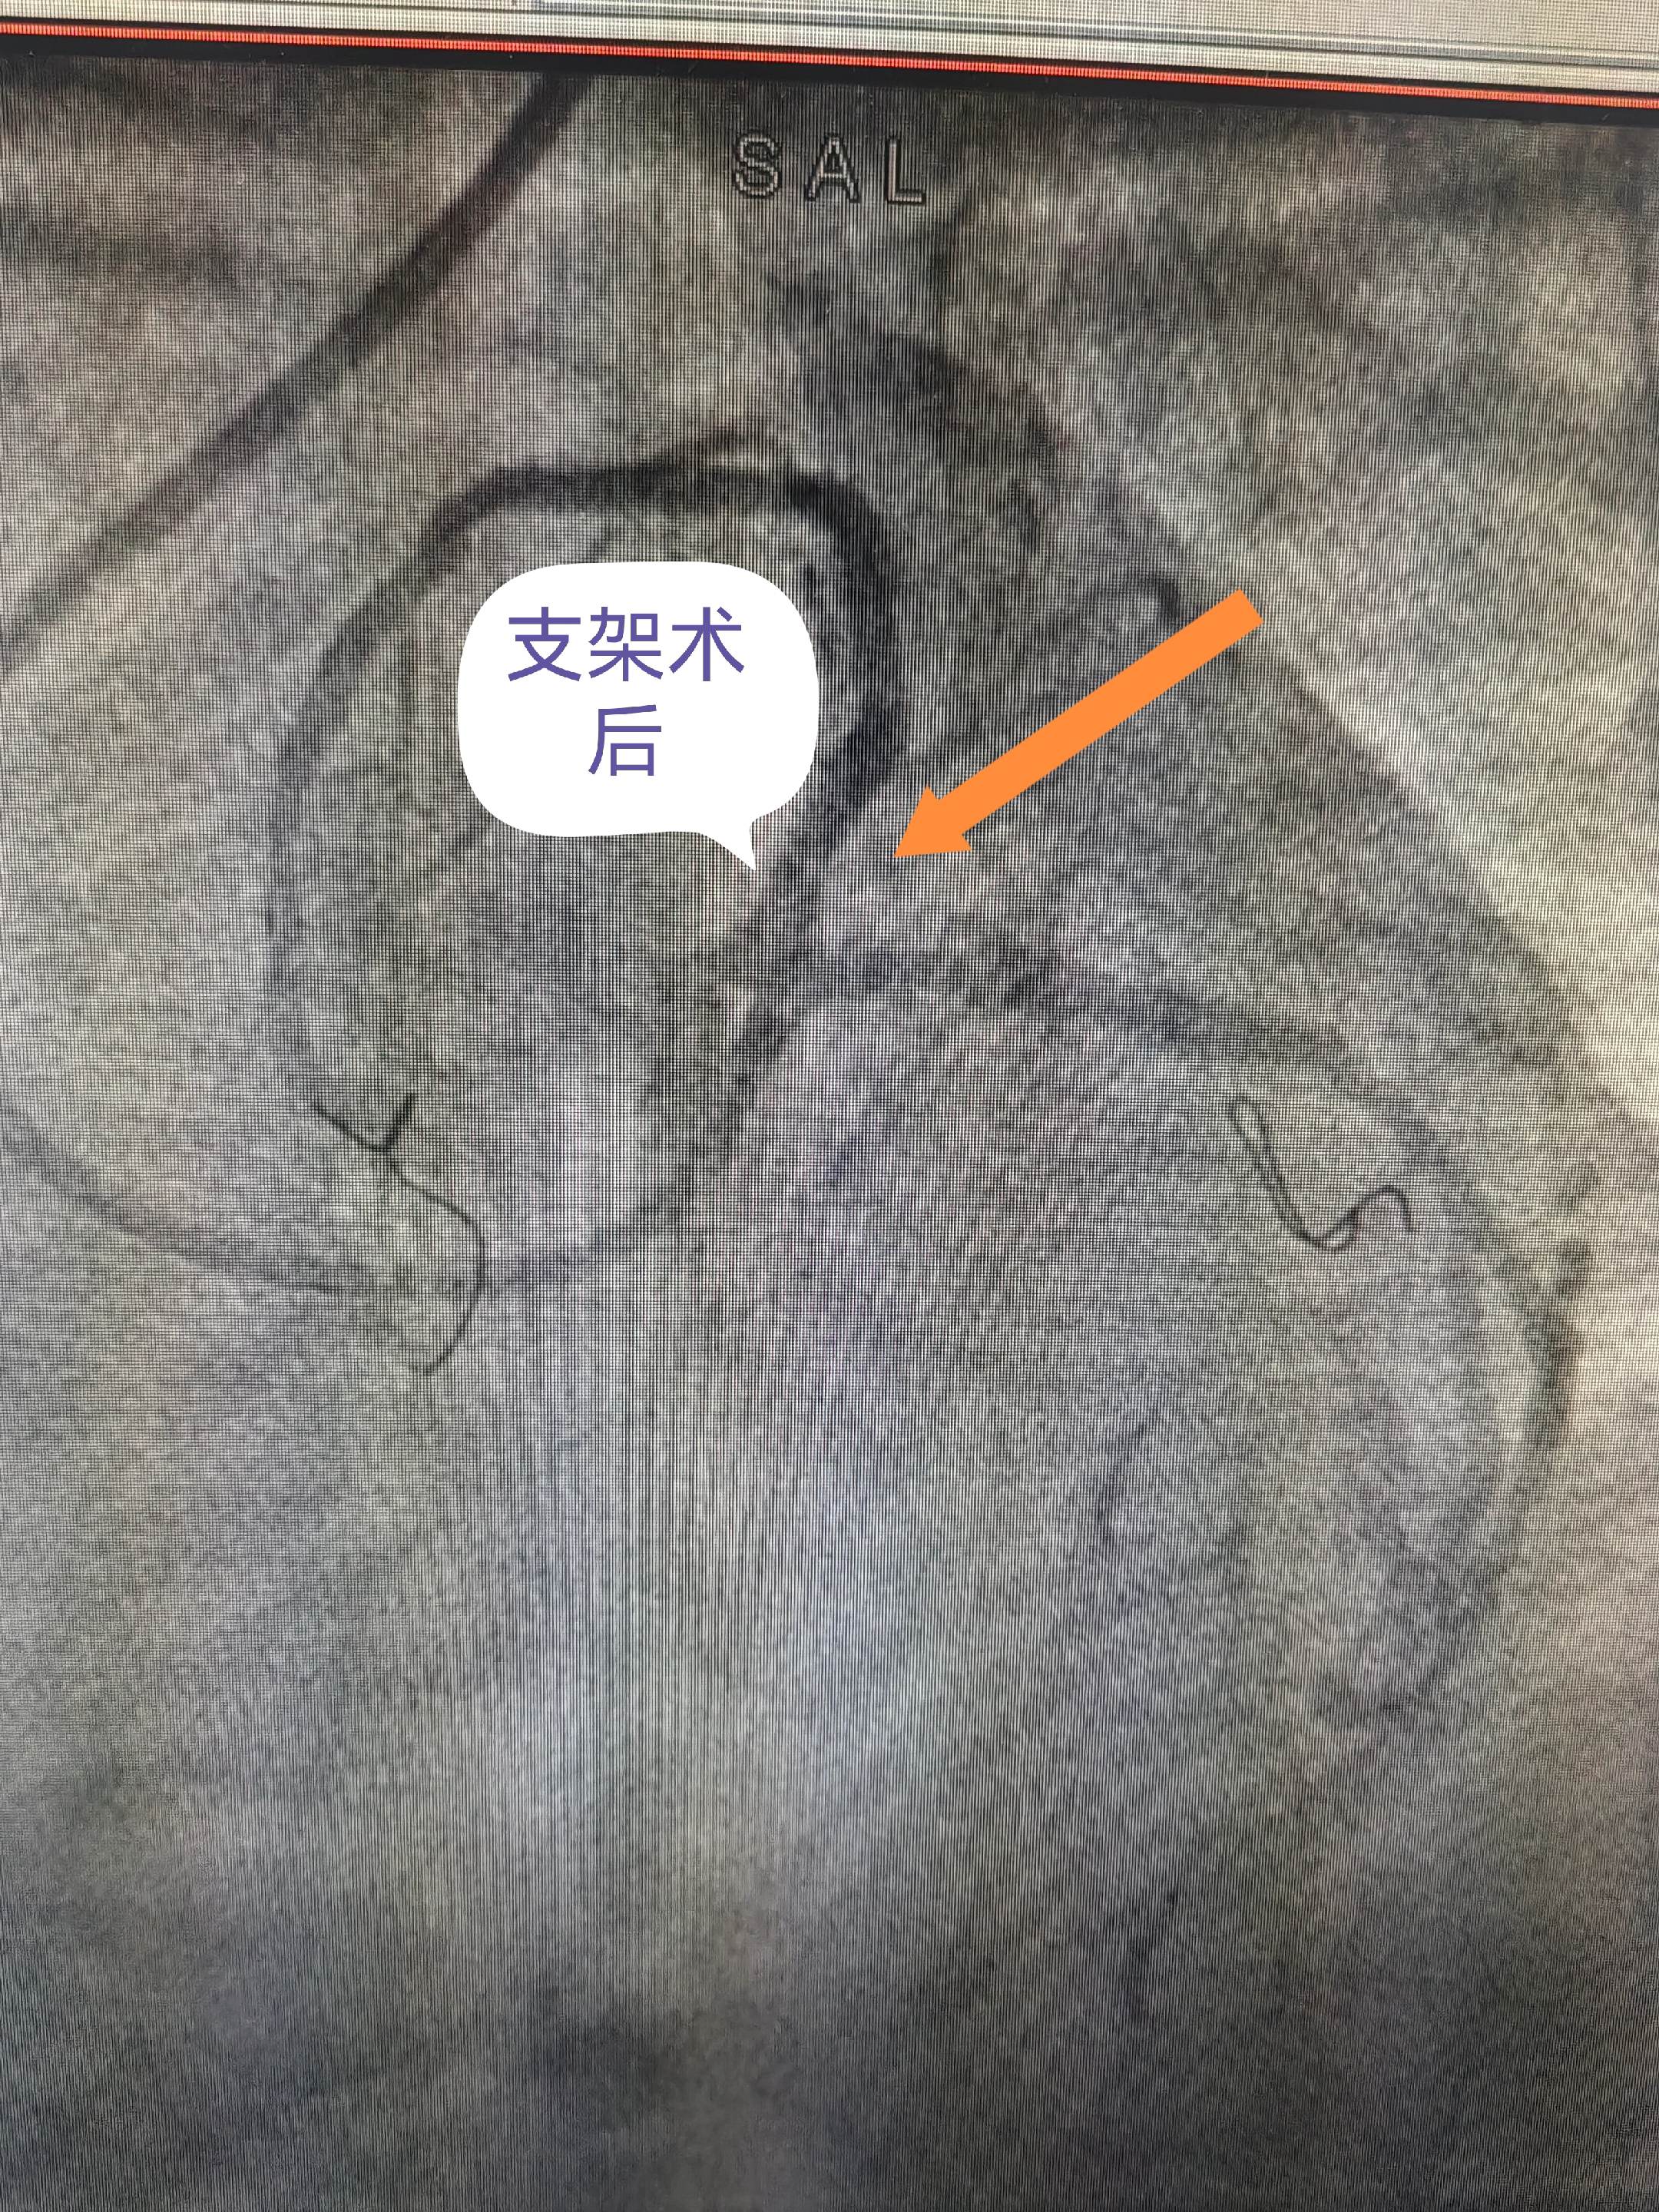

昨天夜班收治三位病人,抢救一人。 今天上午做一台冠脉造影+一台冠脉支架...